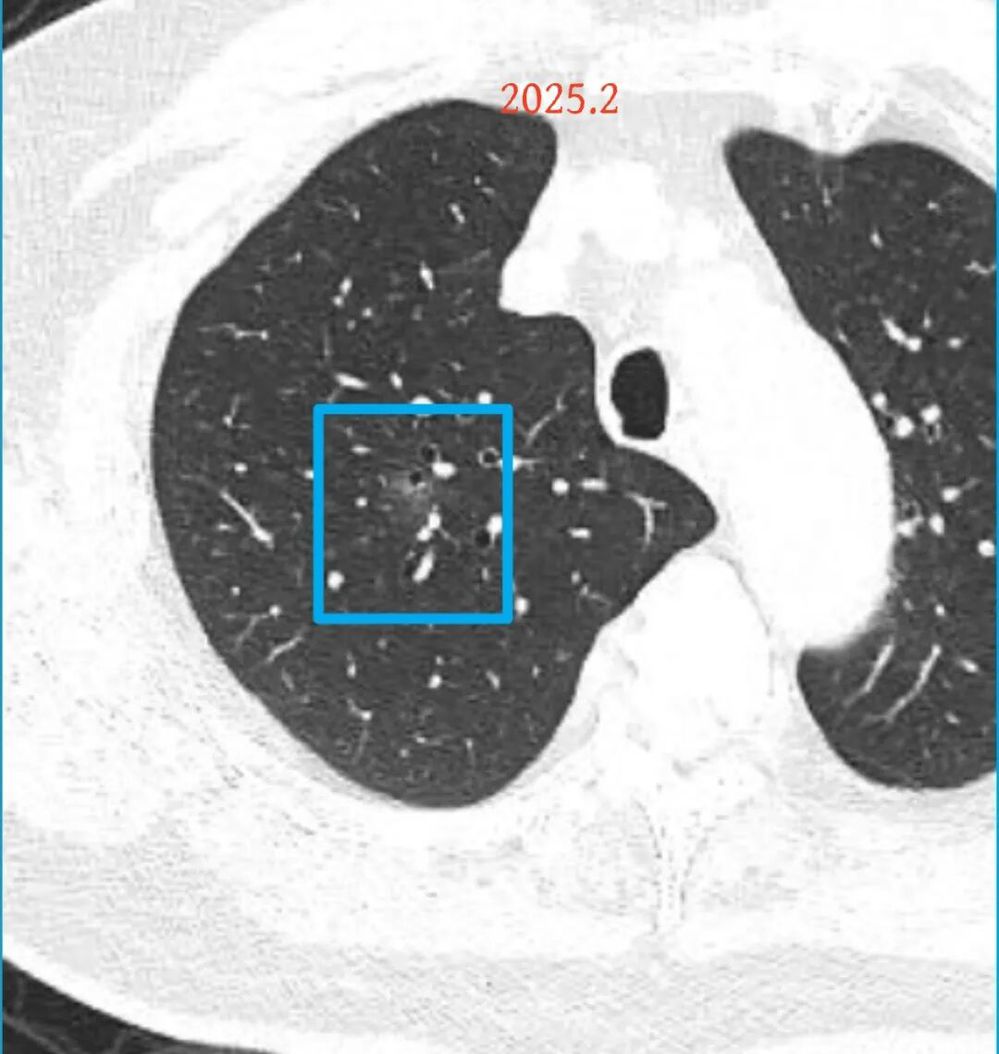

影像展示与分析:

方形的是25年的,红色的主病灶,磨玻璃密度伴少许略偏高点密度,但还说不上典型混合磨玻璃病灶,考虑原位癌或微浸润性腺癌可能性大;蓝色的轮廓与边界欠清,位置靠上叶中央,无法段切或楔切;黄色的多发均淡而纯,分布在两肺。圆形粉色的是主要的两处23年时的样子,对比说不上很明显进展。鉴于若手术得切肺叶,何况两肺他处仍的结节,年纪又74了。我倾向保守点,先6-9个月复查,等进展并风险增加再来考虑怎么办的事。意见供参考!

病灶没有确切纵隔窗可见的实性成分,但与血管关系较为密切。